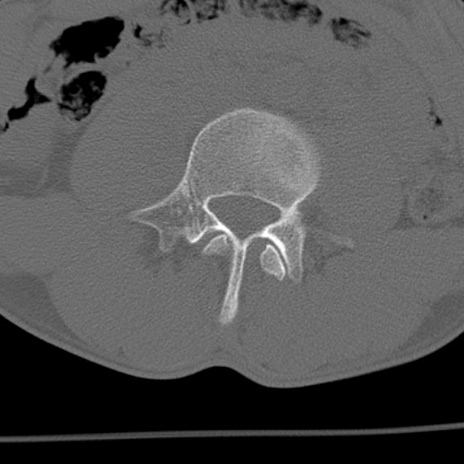

症例3 腰椎CT(横断像)

腰椎CT